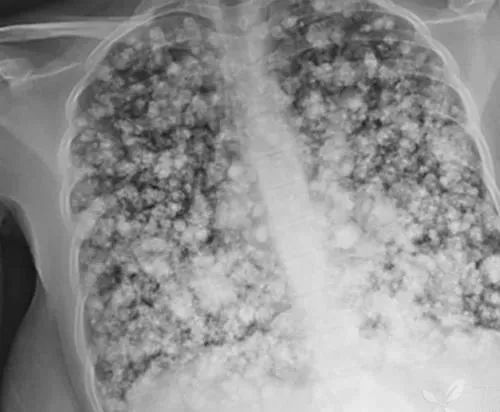

电子烟:电子烟里面的主要成分还是尼古丁,尼古丁本身就有一定的毒害,特别是对血压和神经系统;而电子烟里面的烟雾含有丙二醇等有害物质可以导致心脏病发作和中风。

其次一些商家在电子烟里面添加了过量尼古丁,轻者导致使用者头晕、恶心、呕吐,重者可能导致中毒。